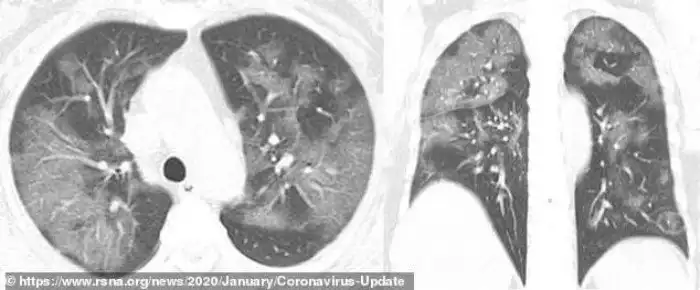

Умерший 44-летний мужчина из Китая жил в Ухани и работал на местном рынке морепродуктов, который, вероятно, стал источником нового вируса. Он был госпитализирован 25 декабря 2019 года после двух недель болезни. Врачи диагностировали у него пневмонию и острый респираторный дистресс синдром. Несмотря на лечение, он умер неделю спустя. Субплевральные уплотнения видны в его легких очень отчетливо. На снимках видно, как легкие со временем, от снимка А до снимка F, все сильнее заполняются жидкостью. Компьютерная томограмма легких 54-летней женщины, подхватившей коронавирус во время поездки в Ухань, показывает схожую картину.

Это - снимки 54-летней женщины, у которой по возвращении из Ухани была диагностировала сильная вирусная пневмония. В ходе лечения врачи давали ей кислород и антибиотики.